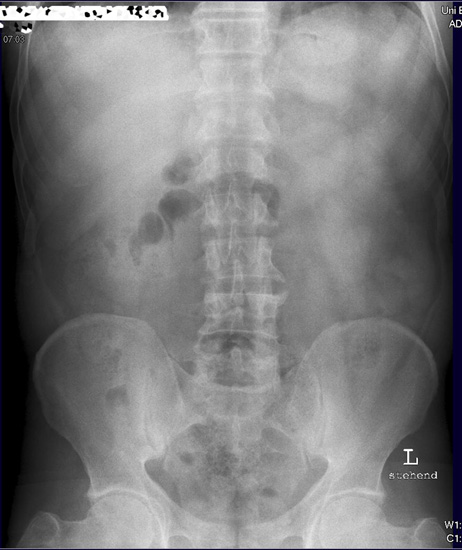

Abdomen im Stehen

Diese Aufnahme ist nicht genügend aussagekräftig, da die Zwerchfelle nicht komplett abgebildet sind. Bei Frage freie Luft sollten immer die Zwerchfelle im Stehen zu stehen sein.

Solch eine Aufnahme müsste noch mal wiederholt werden und etwas höher eingestellt werden. Viele Patienten können auf Grund ihrer abdominellen Beschwerden nicht tief genug einatmen. Deshalb nicht blind abdrücken, sondern genau zum Patienten schauen wie er einatmet, und nicht zu knapp nach oben hin einstellen.